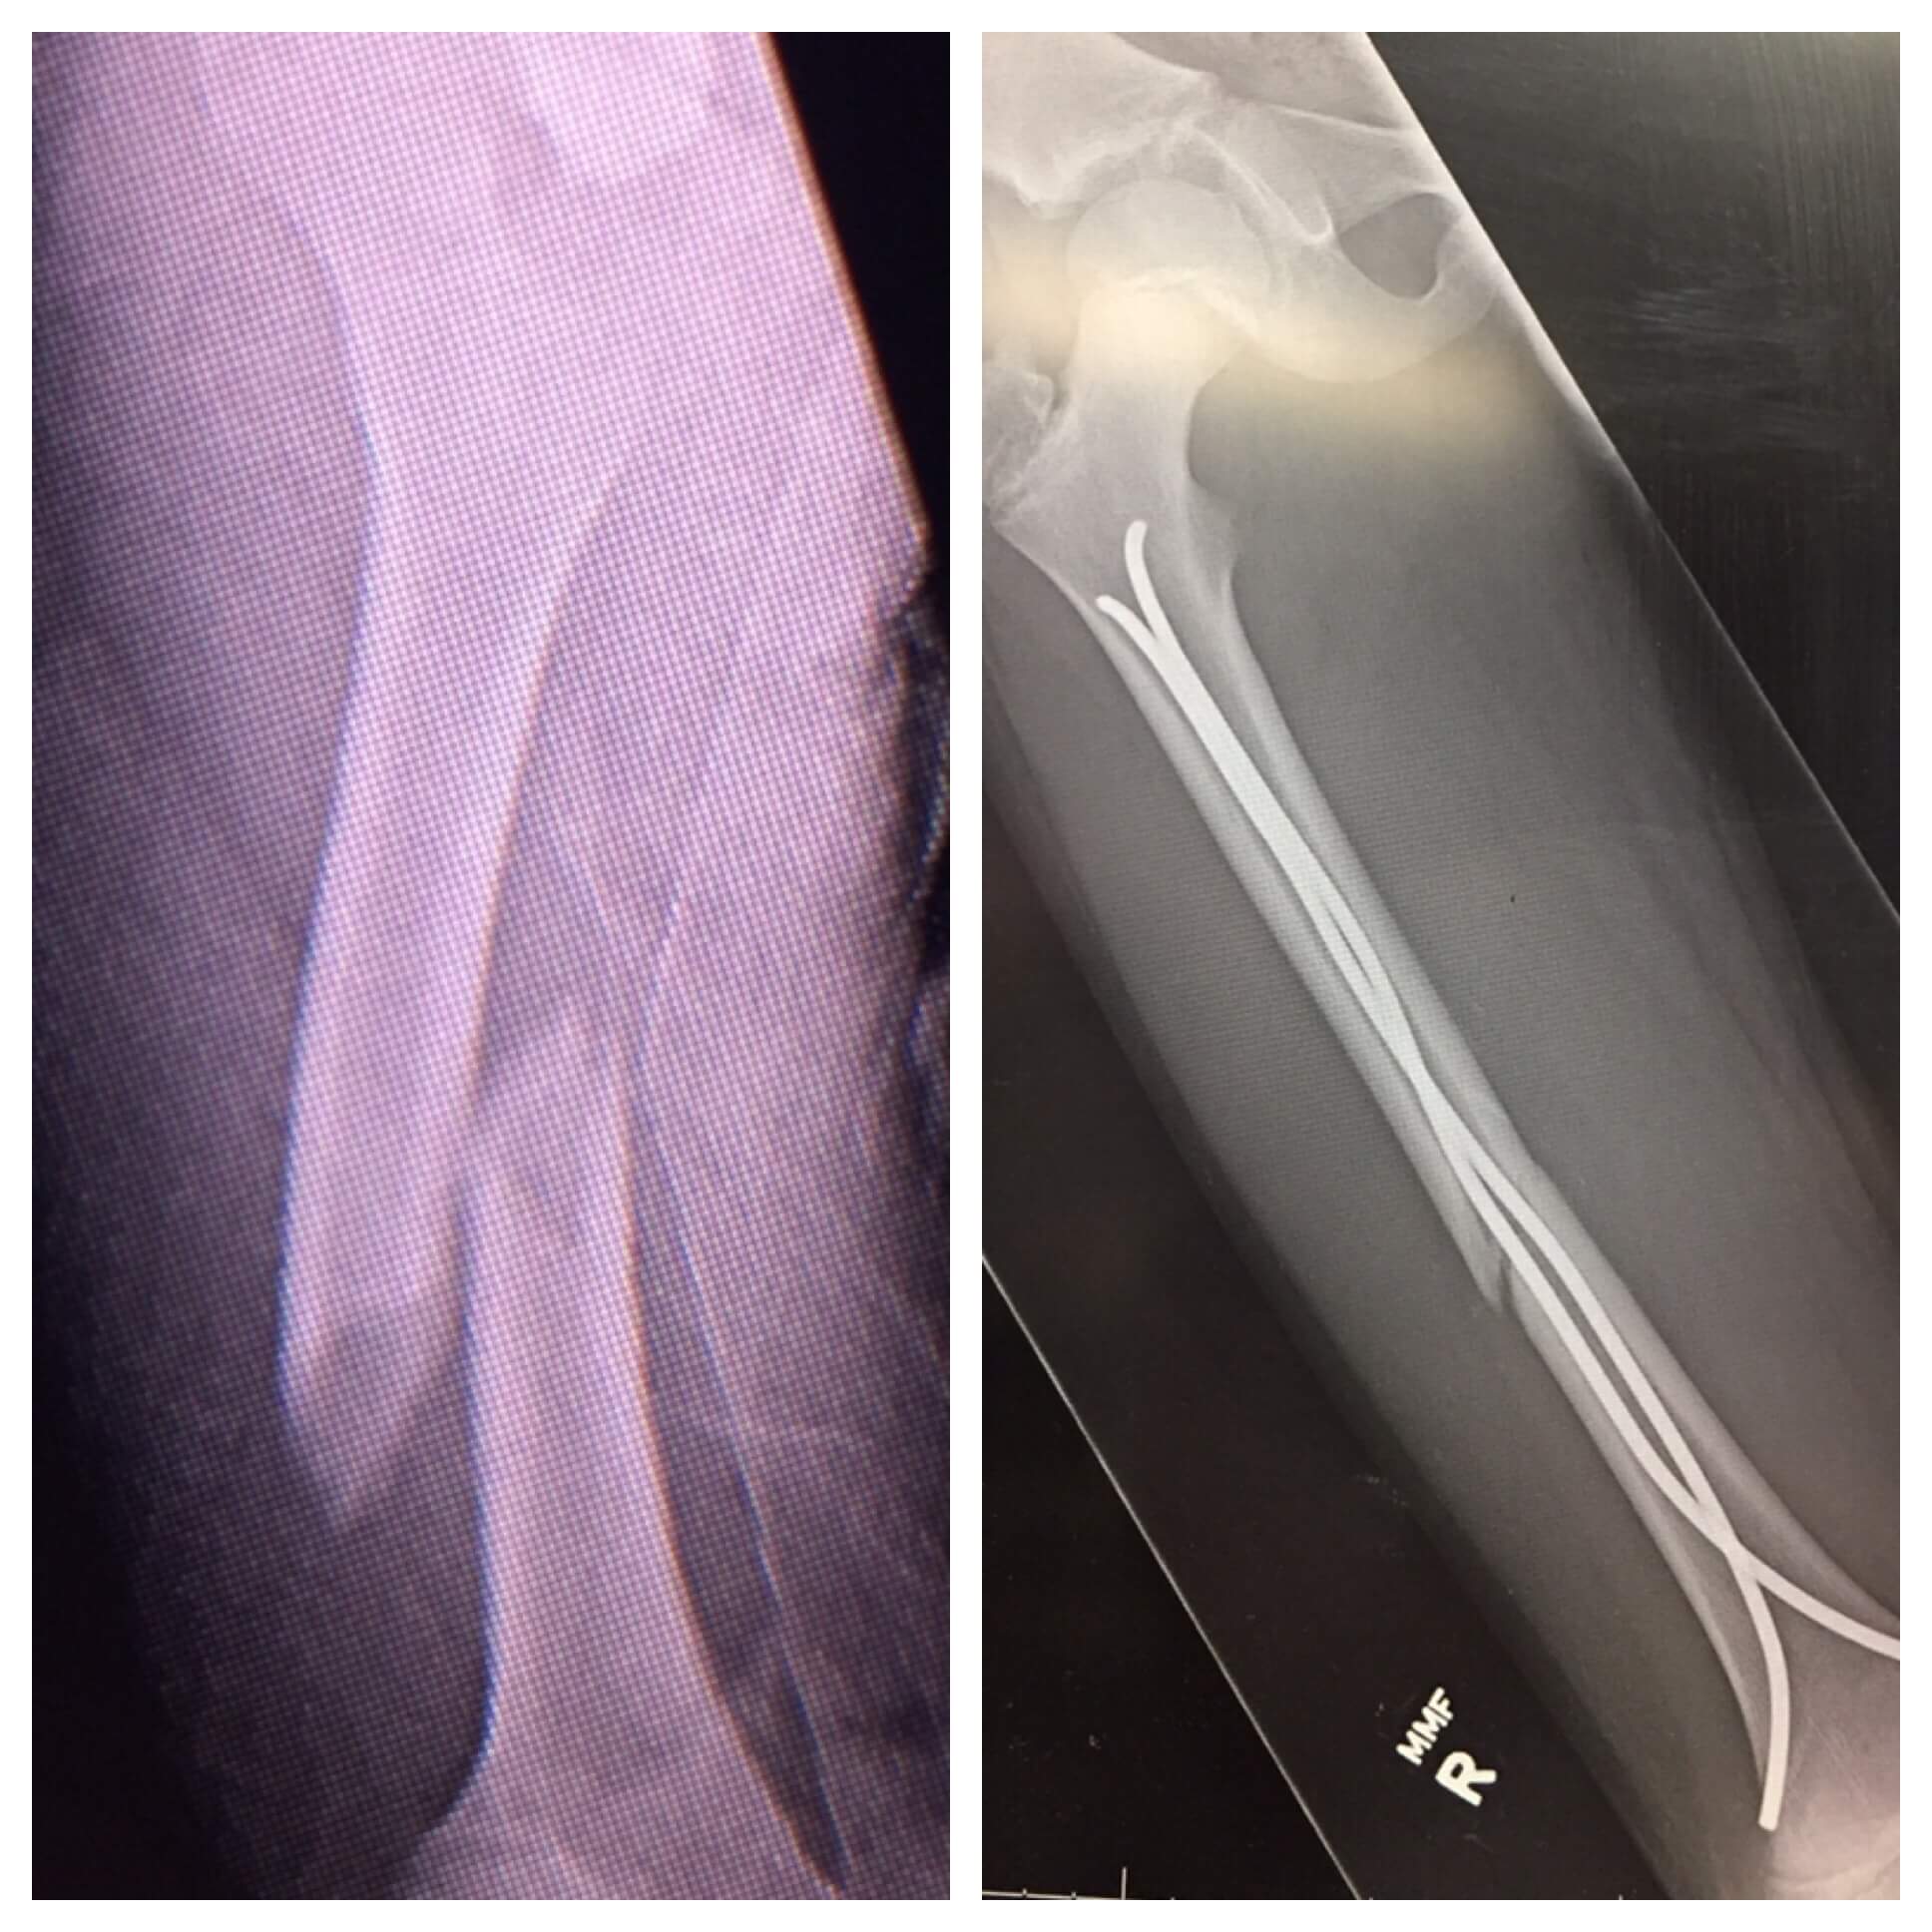

Zach’s surgery took about 2 hours. Dr. Olgun went in to repair his femur with titanium flexible nails. This would allow his bone to continue growing while holding it in place for it to heal properly and his pain to be relieved.

Six months after surgery, Zach was able to have a second surgery to remove the rods from his leg. And about eight weeks after that surgery, Dr. Olgun cleared Zach to return to baseball.